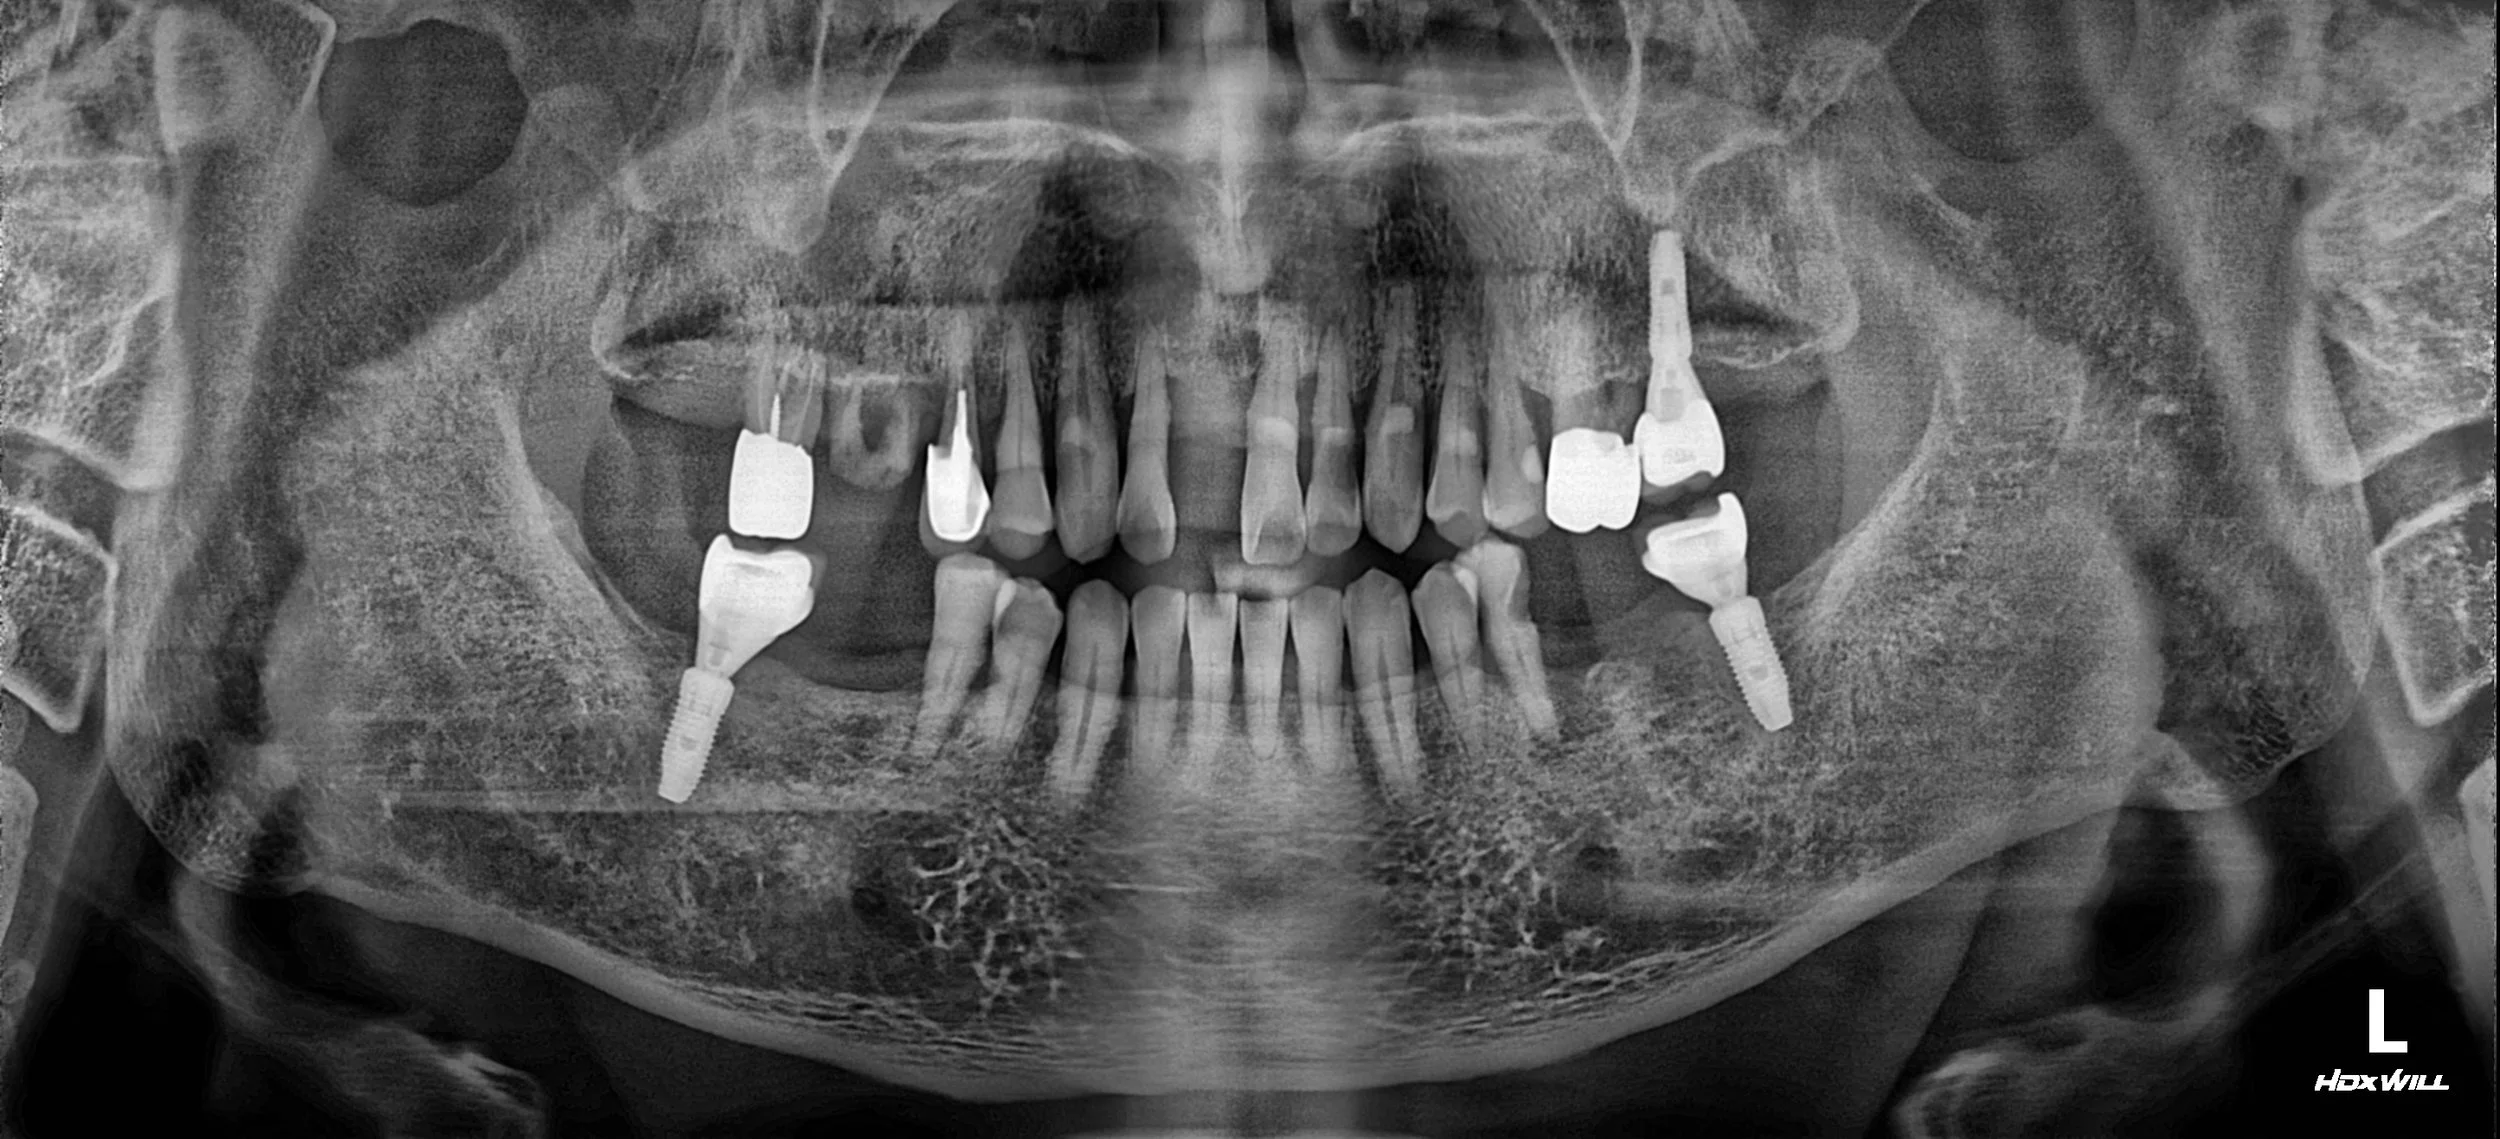

20. Definitive Full-Arch Rehabilitation: Transitioning from Removable Atrophy to Fixed Stability

Severe alveolar bone resorption and periodontal tissue atrophy in a male patient in his 60s. A streamlined full-mouth implant-supported reconstruction for comprehensive functional and aesthetic recovery.